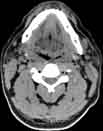

Visible Human male: Sectio transversalis 1207

CT

NMR

Pd T1 T2